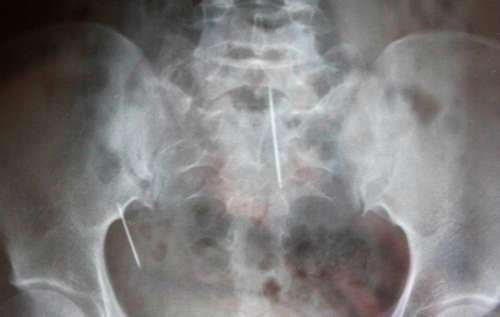

“肚子里有两根缝衣针?怎么可能?”当医生指着X光照片上的两根针状物时,唐明强(化名)怎么也不敢相信女儿唐丽(化名)的肚子里有两根针。

7月30日上午11时许,记者来到市中心医院时,唐丽的手术已经结束。主治医师贾映东向记者展示了这两根刚取出的缝衣针。这是再常见不过的缝衣针,大约4厘米长,看上去已经锈迹斑斑。除了这两枚缝衣针,医生还在唐丽的体内找出了几截分别不到1厘米长的自动铅笔芯!“这种情况我还是第一次碰到!”贾映东告诉记者,缝衣针在体内十分危险,因为它可能随着身体的运动在体内游动,很有可能刺破体内重要器官,甚至威胁到患者的生命。贾医生说,手术很顺利,经过一段时间的恢复就可以出院。

在大约1年前,患者的肚脐开始流“水”。对此,贾医生给出这样的解释,患者的脐尿管没有封闭,这是引起肚脐流“水”的原因。不解的是,手术中医生在唐丽的脐尿管中发现了其中的一根缝衣针。缝衣针为何会出现在脐尿管中,另一名医生作出了一种假设:由于脐尿管没有封闭而流“水”,其实流出的是尿液,味道难闻,患者便用缝衣针(或者铅笔芯)擦进去试图堵上。然而这也仅仅是一种假设,而这种假设也无法解释腹腔中的那根缝衣针的来源。对此,唐明强表示将会继续查证下去,找出女儿体内出现缝衣针的真相。(熊文)